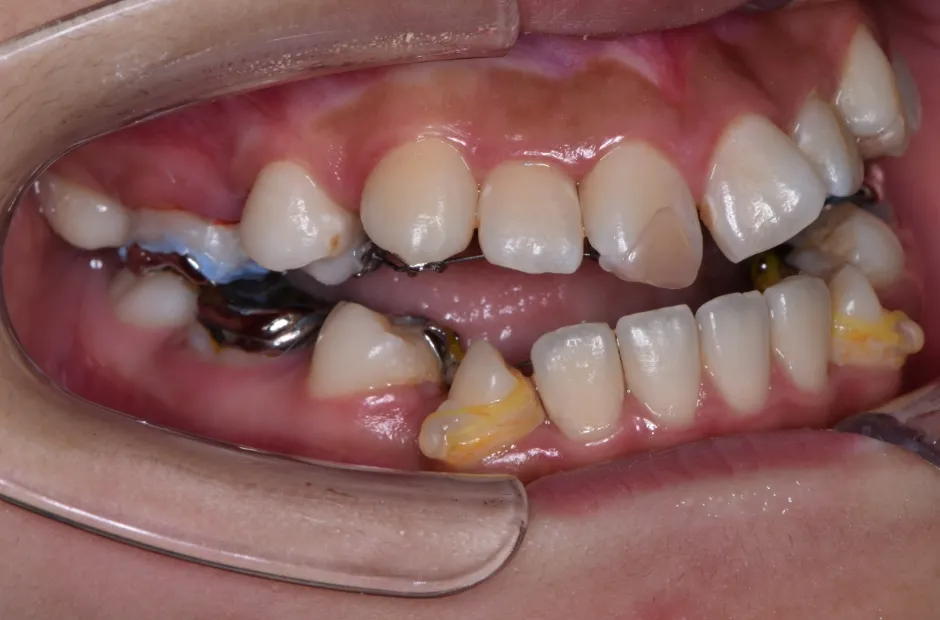

治療症例

ブラケット矯正

前歯部反対咬合

| 診断名・主訴 | 前歯部反対咬合 |

|---|---|

| 年齢・性別 | 14歳・男性 |

| 治療期間・回数 | 1年2か月 |

| 治療に用いた主な装置 | ブラケット矯正 |

| 抜歯部位 | なし |

| 治療費 | 60万円(税抜) |

| リスク・副作用 | 装置による違和感・疼痛・歯肉退縮・歯根吸収・虫歯のリスクなど |

治療前

治療中

治療後